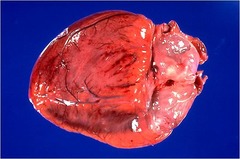

myocardial necrosis coagulative

disease? type of necrosis